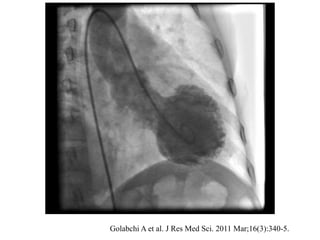

Takotsubo cardiomyopathy

Golabchi A et al. J Res Med Sci. 2011 Mar;16(3):340-5.